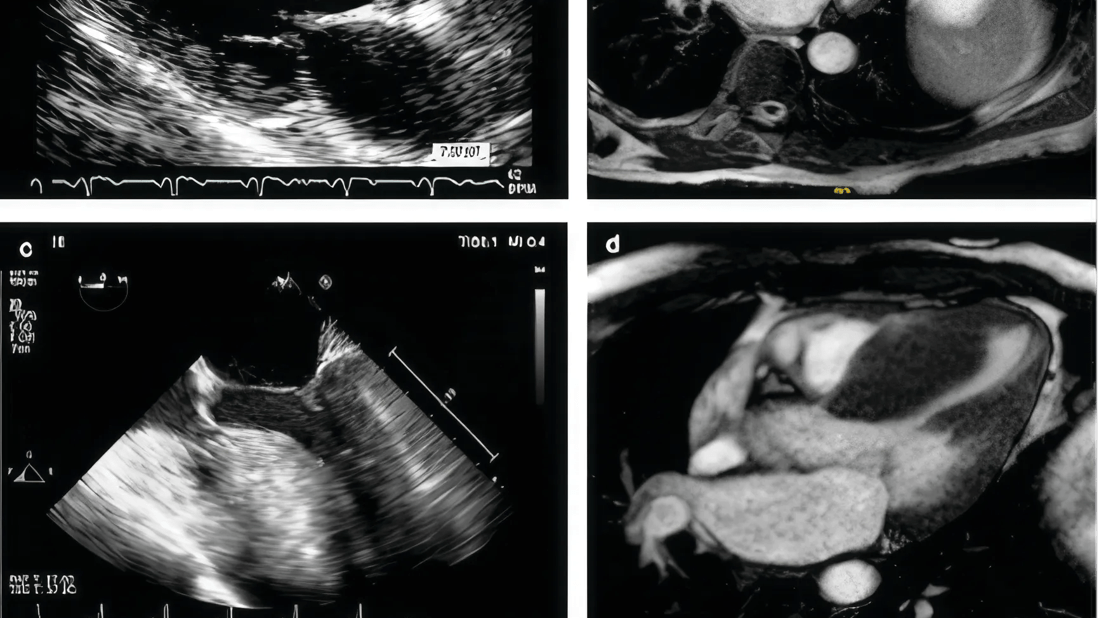

There are infinite configurations of the septum (Figure 1). Cleveland Clinic surgeons review all preoperative imaging studies, including magnetic resonance imaging and echocardiograms, and occasionally can print a 3-dimensional model of the patient’s heart to understand the anatomy.

The operation is carried on through an incision of the initial portion of the aorta that allows to retract the aortic valve leaflets and provide exposure of the complex inner anatomy of the left ventricle including the interventricular septum, the papillary muscles with their chordae, and the mitral valve. Long-toothed forceps and scalpel are used to perform a tailored resection of septal myocardial muscle that starts about 15 mm below the right coronary cusp, away from the membranous septum and the bundle of His, extending longitudinally towards the apex and tapering down laterally as the resection ends in the regions of normal myocardial thickness (Figure 2).